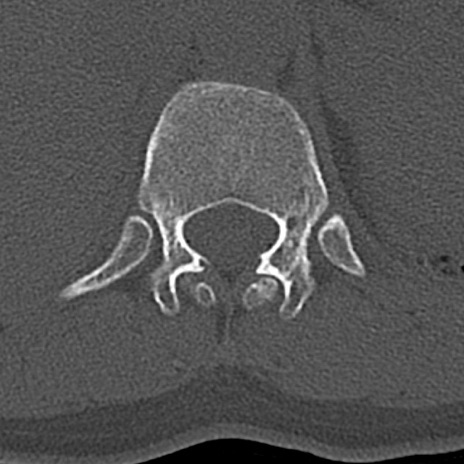

【整形】TIPS症例4 腰椎CT(横断像)

腰椎CT

横断像と矢状断像